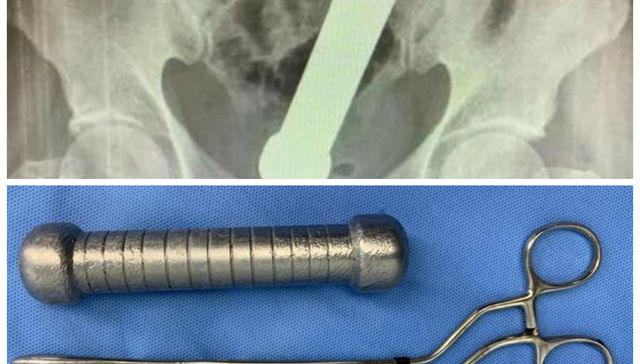

Se sacó un peso de encima

Brasileño fue a parar al hospital luego de introducirse en el ano una mancuerna de 2 kilos